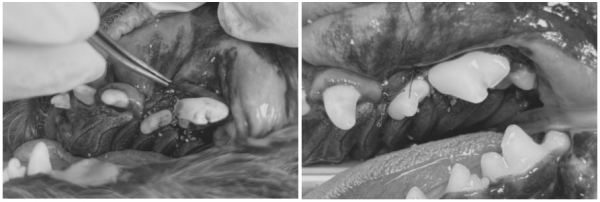

[진행한 치아 치료 과정 GBR/GTR(치조골 재생술)]

치아를 보존할 수 있는 좌측 어금니 부위는

다음과 같은 방식으로 보존 치료를 시행했습니다.

→ 해당 치아의 잇몸을 분리 후,

염증 조직을 제거하고 치은연하 스케일링을 진행한 뒤

de70cef8385ff32e9ecfc65bf523daeb_1766380615_8614.png

뼈 이식재를 해당 부위에 이식하고

차폐막을 삽입한 뒤 안전하게 봉합하였습니다.